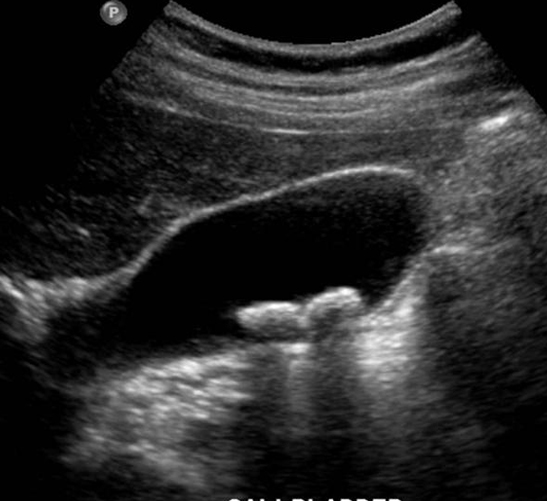

Image echographique

:

C'est la technique de la premier de l'intention pour

explore de calcul vesiculaire , sa sensibilite et sa specifilite

est tres bonne de donnee des signes direct ou indirecte des

voies biliaire intrahepatique( VBIH ) ou des voie biliaire

pricipale ( VBP) . Images echographique direct de

calcul vesiculaire est image hyperechogene en forme C

inverse ,avec de vide aoustique posterieure , sa nombre , la

taille est varie .Localisation peut mobilisee quand on a change

position du maladie " rolling stone sign "

Petite calcule a

infundibulum de la vesicule biliaire . Coupe

echographique recurrent a hypochondre droit |

|

Calcul vesicule biliaire :

Image hyperechogene de 10mm en C forme

avec espace de

vide ascoustique posterieure en voyant tres fine .

Image echographique du foie |